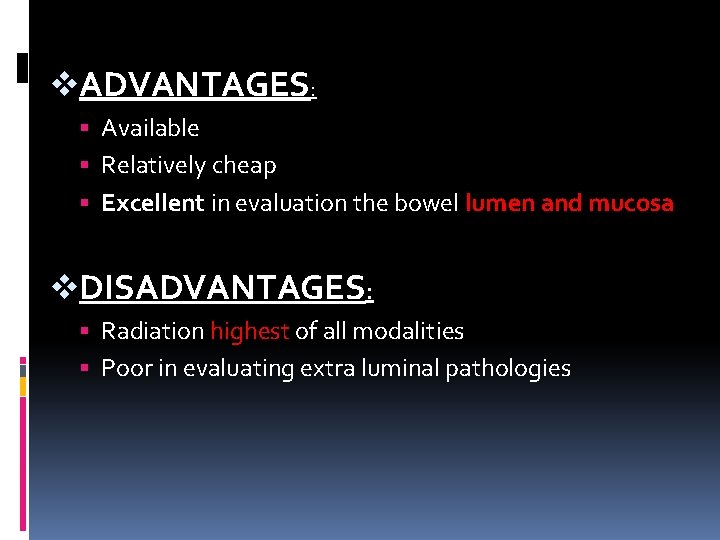

v. ADVANTAGES: Available Relatively cheap Excellent in evaluation the bowel lumen and mucosa v. DISADVANTAGES: Radiation highest of all modalities Poor in evaluating extra luminal pathologies